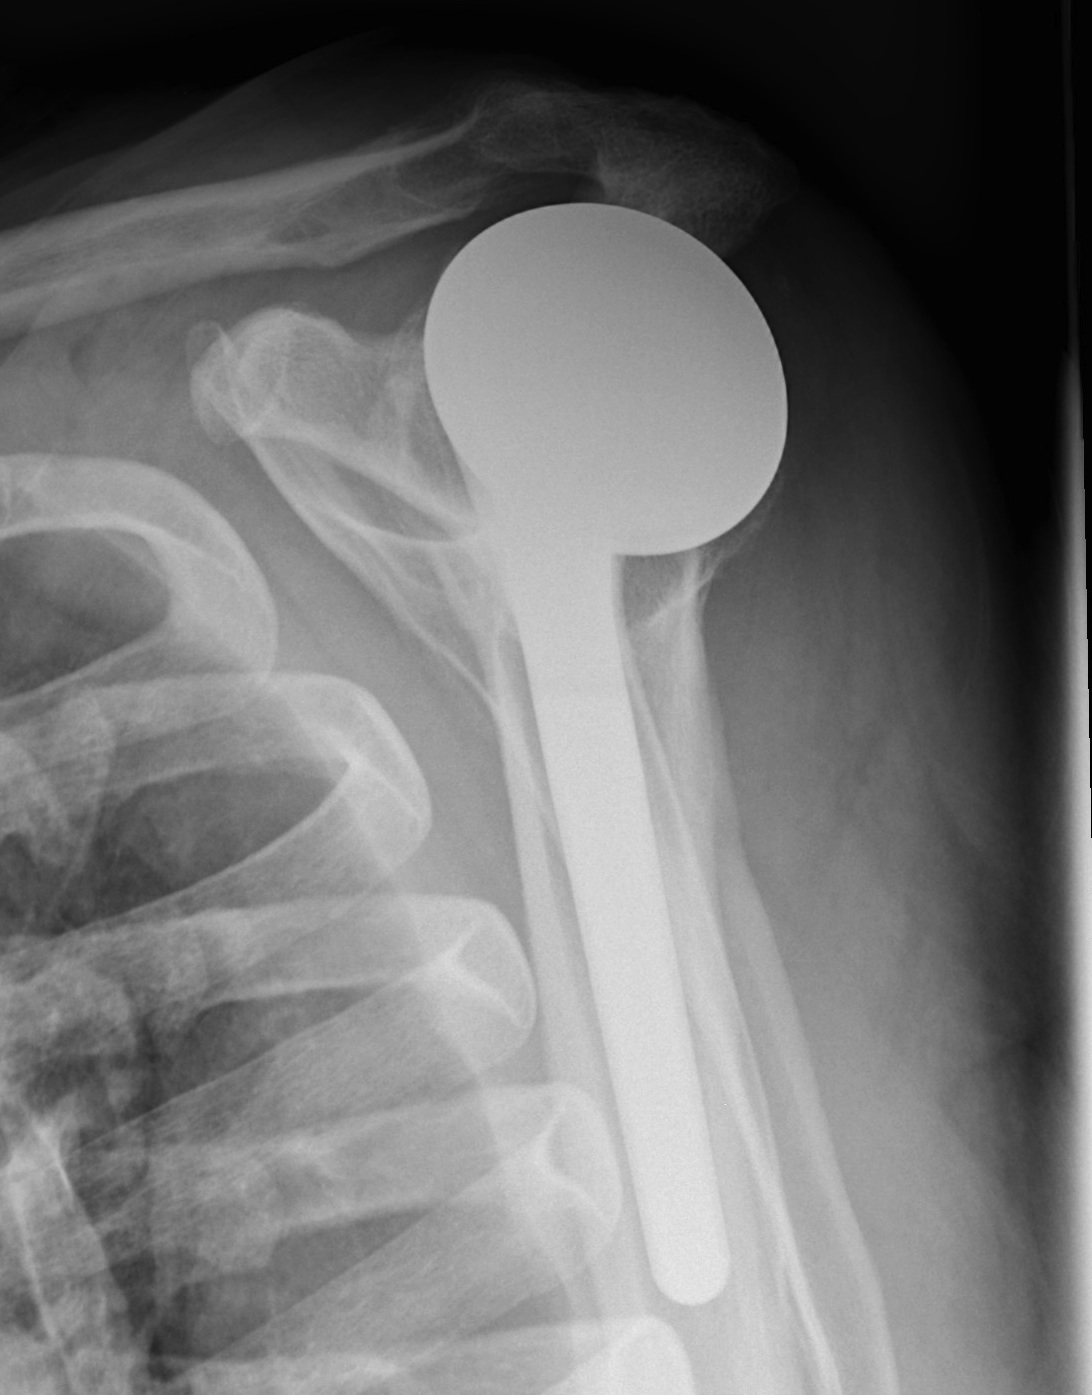

Technique

- extra-articular

Portals

- posterior portal very lateral so can see anterior aspect subacromial space

- port of Wilminton at anterolateral acromion to access SSC

- anterior portal in normal position, slightly more lateral so becomes working portal

Engaging Hill Sachs

- head that translates 50% in all directions

- allows 30o ER with arm at side

- stable posteriorly